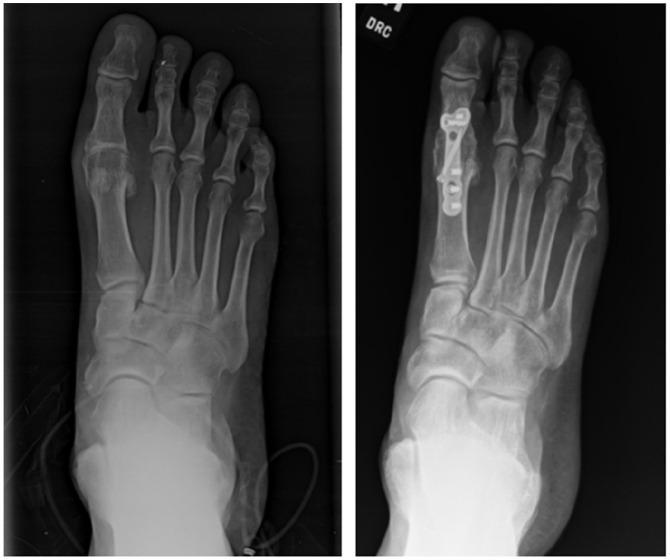

Abstract Image